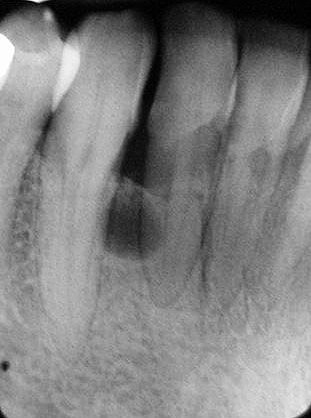

Πλάγια περιοδοντική κύστη .

- Ακτινογραφικά εμφανίζεται σαν καλά περιγεγραμμένη διαύγαση στρογγύλου ή ωοειδούς σχήματος, μεγέθους μικρότερο του 1 cm σε διάμετρο.